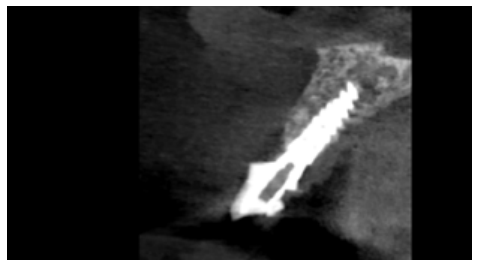

Clinical case: A 32-year-old female patient who attended for a possible root fracture of the upper left central incisor (ULCI), accompanied by a periodontal abscess at the bottom of the vestibule of the same tooth. A clinical and radiological examination established that the prognosis of the ULCI was unfavourable for conservative treatment. After evaluating the clinical features of the case, the treatment plan to extract the ULCI followed immediately by an osseointegrated implant (OII) and loading of a provisional prosthesis on the implant.

The physiological processes that take place after the extraction of a tooth are drastic, as they entail a series of modifications in the soft and hard tissues of the alveolar complex. Mainly, the microvascularisation of the architecture that surrounds the tooth suffers damage and atrophy that culminates in a decrease in the vascular supply provided by the periodontal ligament1-4. This results in a series of resorption processes discussed in this description of a clinical case.

Advances in oral implantology have brought with it new surface treatments for osseointegrated implants (OII), as well as different macroscopic designs and materials. This has been associated with greater primary stability of the OII and a better prognosis. The current trend in the field of implantology has been an evolution from conventional loading of the OII to immediate loading, due to the greater functional and aesthetic demands of society and patients5.